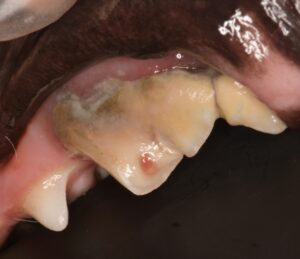

左第四前臼歯:複雑性歯冠破折

破折により、歯の中の神経の露出(露髄)がみられました。

さらに歯科レントゲンを撮影すると、顎の骨が溶けているが分かりました。